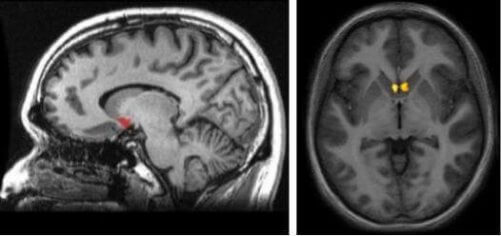

Şimdi bu beyin yapısının nerede olduğunu kendinize soruyor olabilirsiniz. Kavramsallaştırmak için, kaudat çekirdek, putamen ve septum arasındaki bağlantı noktasında korteks altı alanı gözünüzün önüne getirin. Beynin ödül merkezinin en önemli yönlerinden biri yeridir, çünkü beynin dopamin ile harekete geçen yolunun bir parçasıdır. Bu mezolimbik yoldur. Beyniniz, zevkli ve tatmin edici deneyimler geçirdiğinize inandığında, sizi uyarmaktan sorumludur.

Beyin yarı kürelerinin her birinin kendine ait çekirdekleri vardır. Bu şekilde dopamin ile idare edilen ödül sistemi beynin her iki tarafına da ulaşır. Bu yapı aynı zamanda bazal gangliyanın da bir parçasıdır. Bu nedenle, beynin ödül merkezinin en önemli özelliklerinden biri, beynin diğer bölümlerine ne ölçüde bağlı olduğudur.